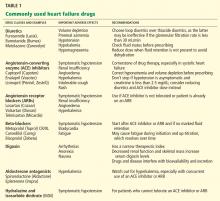

Quality, frailty, and common sense

Congestive heart failure, as noted in the review by Samala et al in this issue of the Journal, is more prevalent in the elderly. Particularly in the frail elderly, managing severe congestive heart failure poses ethical, socioeconomic, and medical challenges. The presence of even subtle cognitive impairment requires detailed dialogue with family and caregivers about medications and about symptoms that warrant a trip to the emergency room. Patients on a fixed income may not be able to afford their medications and thus may use them sporadically. And the preprepared foods they often eat are laden with sodium.

The symptoms of congestive heart failure may easily go unrecognized or be attributed to other common problems. Sorting out the reasons for exertional fatigue, especially a generalized sense of fatigue, can be particularly vexing. Anemia and sarcopenia can directly cause exertional fatigue or “weakness” but may also exacerbate heart failure and cause similar symptoms. Pharmacologic and dietary causes for volume overload must be sought. Even intermittent use of over-the-counter nonsteroidal anti-inflammatory drugs can be problematic.

Severe congestive heart failure is a lethal disease. Current quality guidelines for its treatment emphasize the use of multiple drugs and devices. Yet vasoactive drugs may not be well tolerated in frail patients, who are particularly vulnerable to orthostatic hypotension and cerebral hypoperfusion. Digoxin, of marginal benefit in younger patients without tachyarrhythmias, has an even more tenuous risk-benefit ratio in the frail elderly. Beta-blockers may cause fatigue and depression, and even low-dose diuretics can exacerbate symptoms of bladder dysfunction. Previously implanted defibrillators may be inconsistent with the patient’s current end-of-life desires.

Ideal management of the genuinely frail elderly patient with severe congestive heart failure is not always a matter of ventricular assist devices, biventricular pacers, or angiotensin-converting enzyme inhibitors. At some point, referral to palliative care resources, guided by informed input from the patient, family members, and caregivers, may be the most appropriate high-quality care that we can (and should) offer.

Heart failure in frail, older patients: We can do ‘MORE’

Mr. R. is an 85-year-old with congestive heart failure; the last time his ejection fraction was measured it was 30%. He also has hypertension, coronary artery disease (for which he underwent triple-vessel coronary artery bypass grafting), osteoarthritis, hyperlipidemia, and chronic obstructive pulmonary disease. He currently takes lisinopril (Zestril), carvedilol (Coreg), aspirin, clopidogrel (Plavix), digoxin, simvastatin (Zocor), furosemide (Lasix), an albuterol inhaler (Proventil), and over-the-counter naproxen (Naprosyn), the last two taken as needed.

Accompanied by his daughter, Mr. R. comes to see his primary care physician for a routine follow-up visit. He says he feels fine and has no shortness of breath or chest pain, but he feels light-headed at times, especially when he gets out of bed. He also mentions that he is bothered with having to get up three to four times at night to urinate.

On further questioning, he relates that he uses a cane to walk around the house and gets short of breath when walking from his bed to the bathroom and from one room to the next. He can feed himself, but he needs assistance with bathing and getting dressed.

Mr. R. admits that he has been feeling lonely since his wife died about a year ago. He now lives with his daughter and her family, and they all get along well. His daughter mentions that over the last 6 months he has not been eating well, that he appears to have lost interest in doing some of the things that he used to enjoy, and that he has lost weight. She adds that he has fallen twice in the last month.

On physical examination, Mr. R. is without distress but appears weak. He answers all questions appropriately, although his affect is flat and his daughter fills in some of the details.

Supine, his blood pressure is 160/90 mm Hg and his heart rate is 75; immediately after standing up he feels dizzy and his blood pressure drops to 120/60 mm Hg with a heart rate of 110. Three months ago he weighed 155 pounds (70.3 kg); today he weighs 145 pounds (65.9 kg).

His neck veins are not distended. On chest auscultation, bibasilar coarse crackles are heard, as well as a systolic murmur (grade 2 on a scale of 6), loudest in the second intercostal space at the right parasternal border. No peripheral edema is detected. His Mini-Mental State Exam score is 22 out of 30.

What changes, if any, should be made in Mr. R.’s management? What advice should the primary care physician give Mr. R. and his daughter about the course of his heart failure?

THE IMPORTANCE OF COMPLETE CARE

Mr. R. has multiple convoluted medical issues that plague many elderly patients with heart failure. To provide optimal care to patients like him, physicians need to draw on knowledge from the fields of internal medicine, geriatrics, and cardiology.

In this paper, we discuss how diagnosing and managing heart failure is different in elderly patients. We emphasize the importance of complete care of frail elderly patients, highlighting the pharmacologic and nonpharmacologic interventions that are available. Finally, we will return to Mr. R. and discuss a comprehensive plan for him.

HEART FAILURE, FRAILTY, DISABILITY ARE ALL CONNECTED

The ability to bounce back from physical insults, chiefly medical illnesses, sharply declines in old age. As various stressors accumulate, physical deterioration becomes inevitable. While some older adults can avoid going down this path of morbidity, in an increasing number of frail elderly patients, congestive heart failure inescapably assumes a complicated course.

Frailty is a state of increased vulnerability to stressors due to age-related declines in physiologic reserve.1 Two elements intimately related to frailty are comorbidity and disability.

Fried et al2 analyzed data from more than 5,000 older men and women in the Cardiovascular Health Study and concluded that comorbidity (ie, having two or more chronic diseases) is a risk factor for frailty, which in turn results in disability, falls, hospitalizations, and death.

The relationship between congestive heart failure and frailty is complex. Not only does heart failure itself result in frailty, but its multiple therapies can put additional stress on a frail patient. In addition, the heart failure and its treatments can negatively affect coexisting disorders (Figure 1).

BY THE NUMBERS

Heart failure is largely a disorder of the elderly, and as the US population ages, heart failure is rising in prevalence to epidemic numbers.3 The median age of patients admitted to the hospital because of heart failure is 75,4 and patients age 65 and older account for more than 75% of heart failure hospitalizations.5 Every year, in every 1,000 people over age 65, nearly 10 new cases of heart failure are diagnosed.6

Before age 70, men are affected more than women, but the opposite is true at age 70 and beyond. The reason for this reversal is that women live longer and have a better prognosis, as the cause of heart failure in most women is diastolic dysfunction secondary to hypertension rather than systolic dysfunction due to coronary artery disease, as in most men.7

Heart failure is costly and generally has a poor prognosis. The total cost of treating it reached a staggering $37.2 billion in 2009, and it was the leading cause of Medicare hospital admissions.6 Heart failure is the primary cause or a contributory cause of death in about 290,000 patients each year, and the rate of death at 1 year is an astonishing 1 in 5.6 The median survival time after diagnosis is 2.3 to 3.6 years in patients ages 67 to 74, and it is considerably shorter—1.1 to 1.6 years—in patients age 85 and older.8